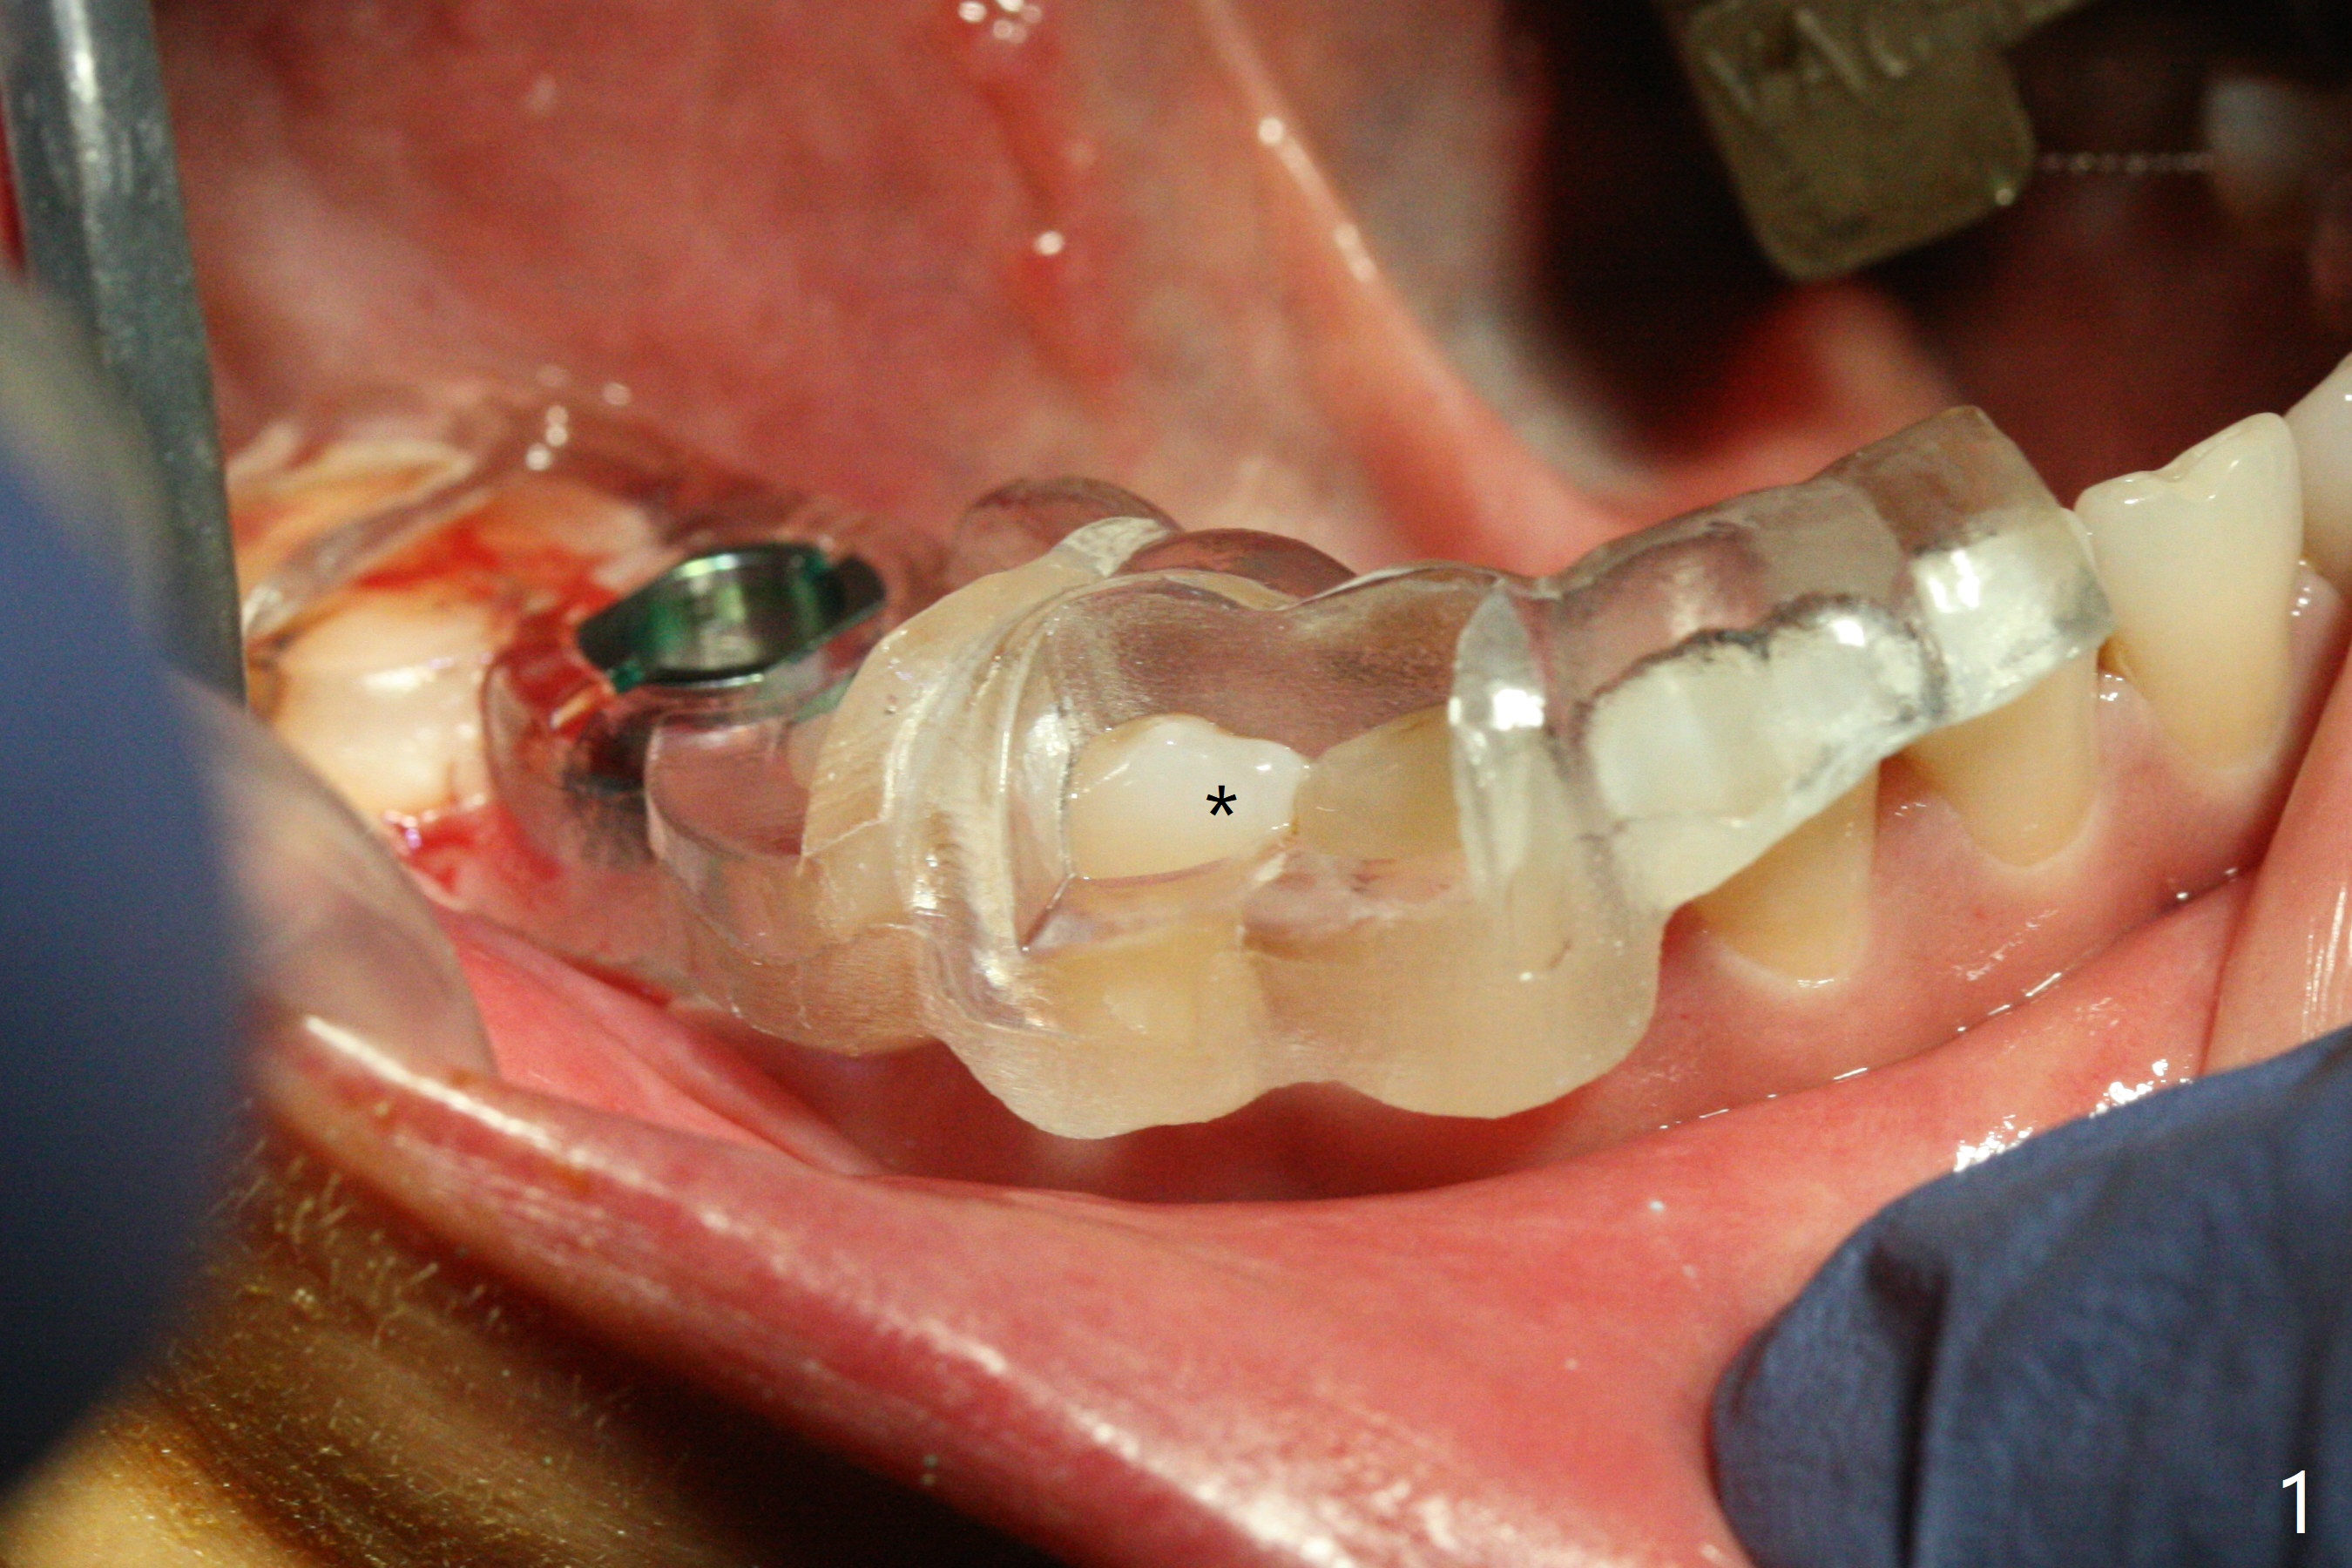

A 5x10 mm implant is placed at #30 with a surgical guide (Fig.1 *) in 10 minutes. The most amazing part of this surgery is that the guide allows you to place the implant at the precise level care-free (~ 1 mm subcrestal, Fig.2,3). Everything happens so quick that when a 5.5x3 mm healing abutment is placed (Fig.4), you are pleased to feel that the implant is stable (Fig.5). You could not ask for anymore. The fearful patient reports no postop pain. The implant is placed as planned (Fig.6, overlap image provided by the guide designer, Jennifer). The patient returns for impression nearly 2 months postop (Fig.7,8). It appears that the implant has osteointegrated without bone loss (Fig.7). The soft tissue is healthy around the just placed cementation abutment (Fig.8 (5.2x4(2) mm)). When the permanent crown is seated initially 2.5 months postop, the mesial contact is slightly tight and the occlusion is high. Bitewing shows the distal open margin (Fig.9 >). After mesial contact adjustment, the patient feels that the occlusion is better. With further occlusal adjustment, the crown is cemented without distal open margin (Fig.10). The patient returns to her home country for 3 months. The implant is doing well 3.5 months post cementation; impression is taken for #14 surgical guide.